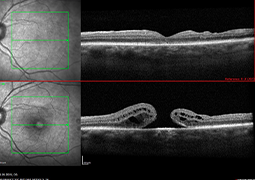

- Novinky v skríningu retinopatie prematúrnych detí. Naše skúsenosti s novinkami v odporučeniach pre skríning retinopatie predčasne narodených detí